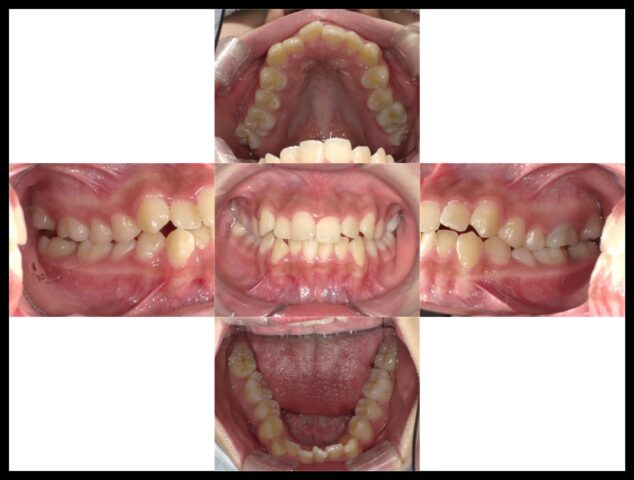

症例紹介

before

after